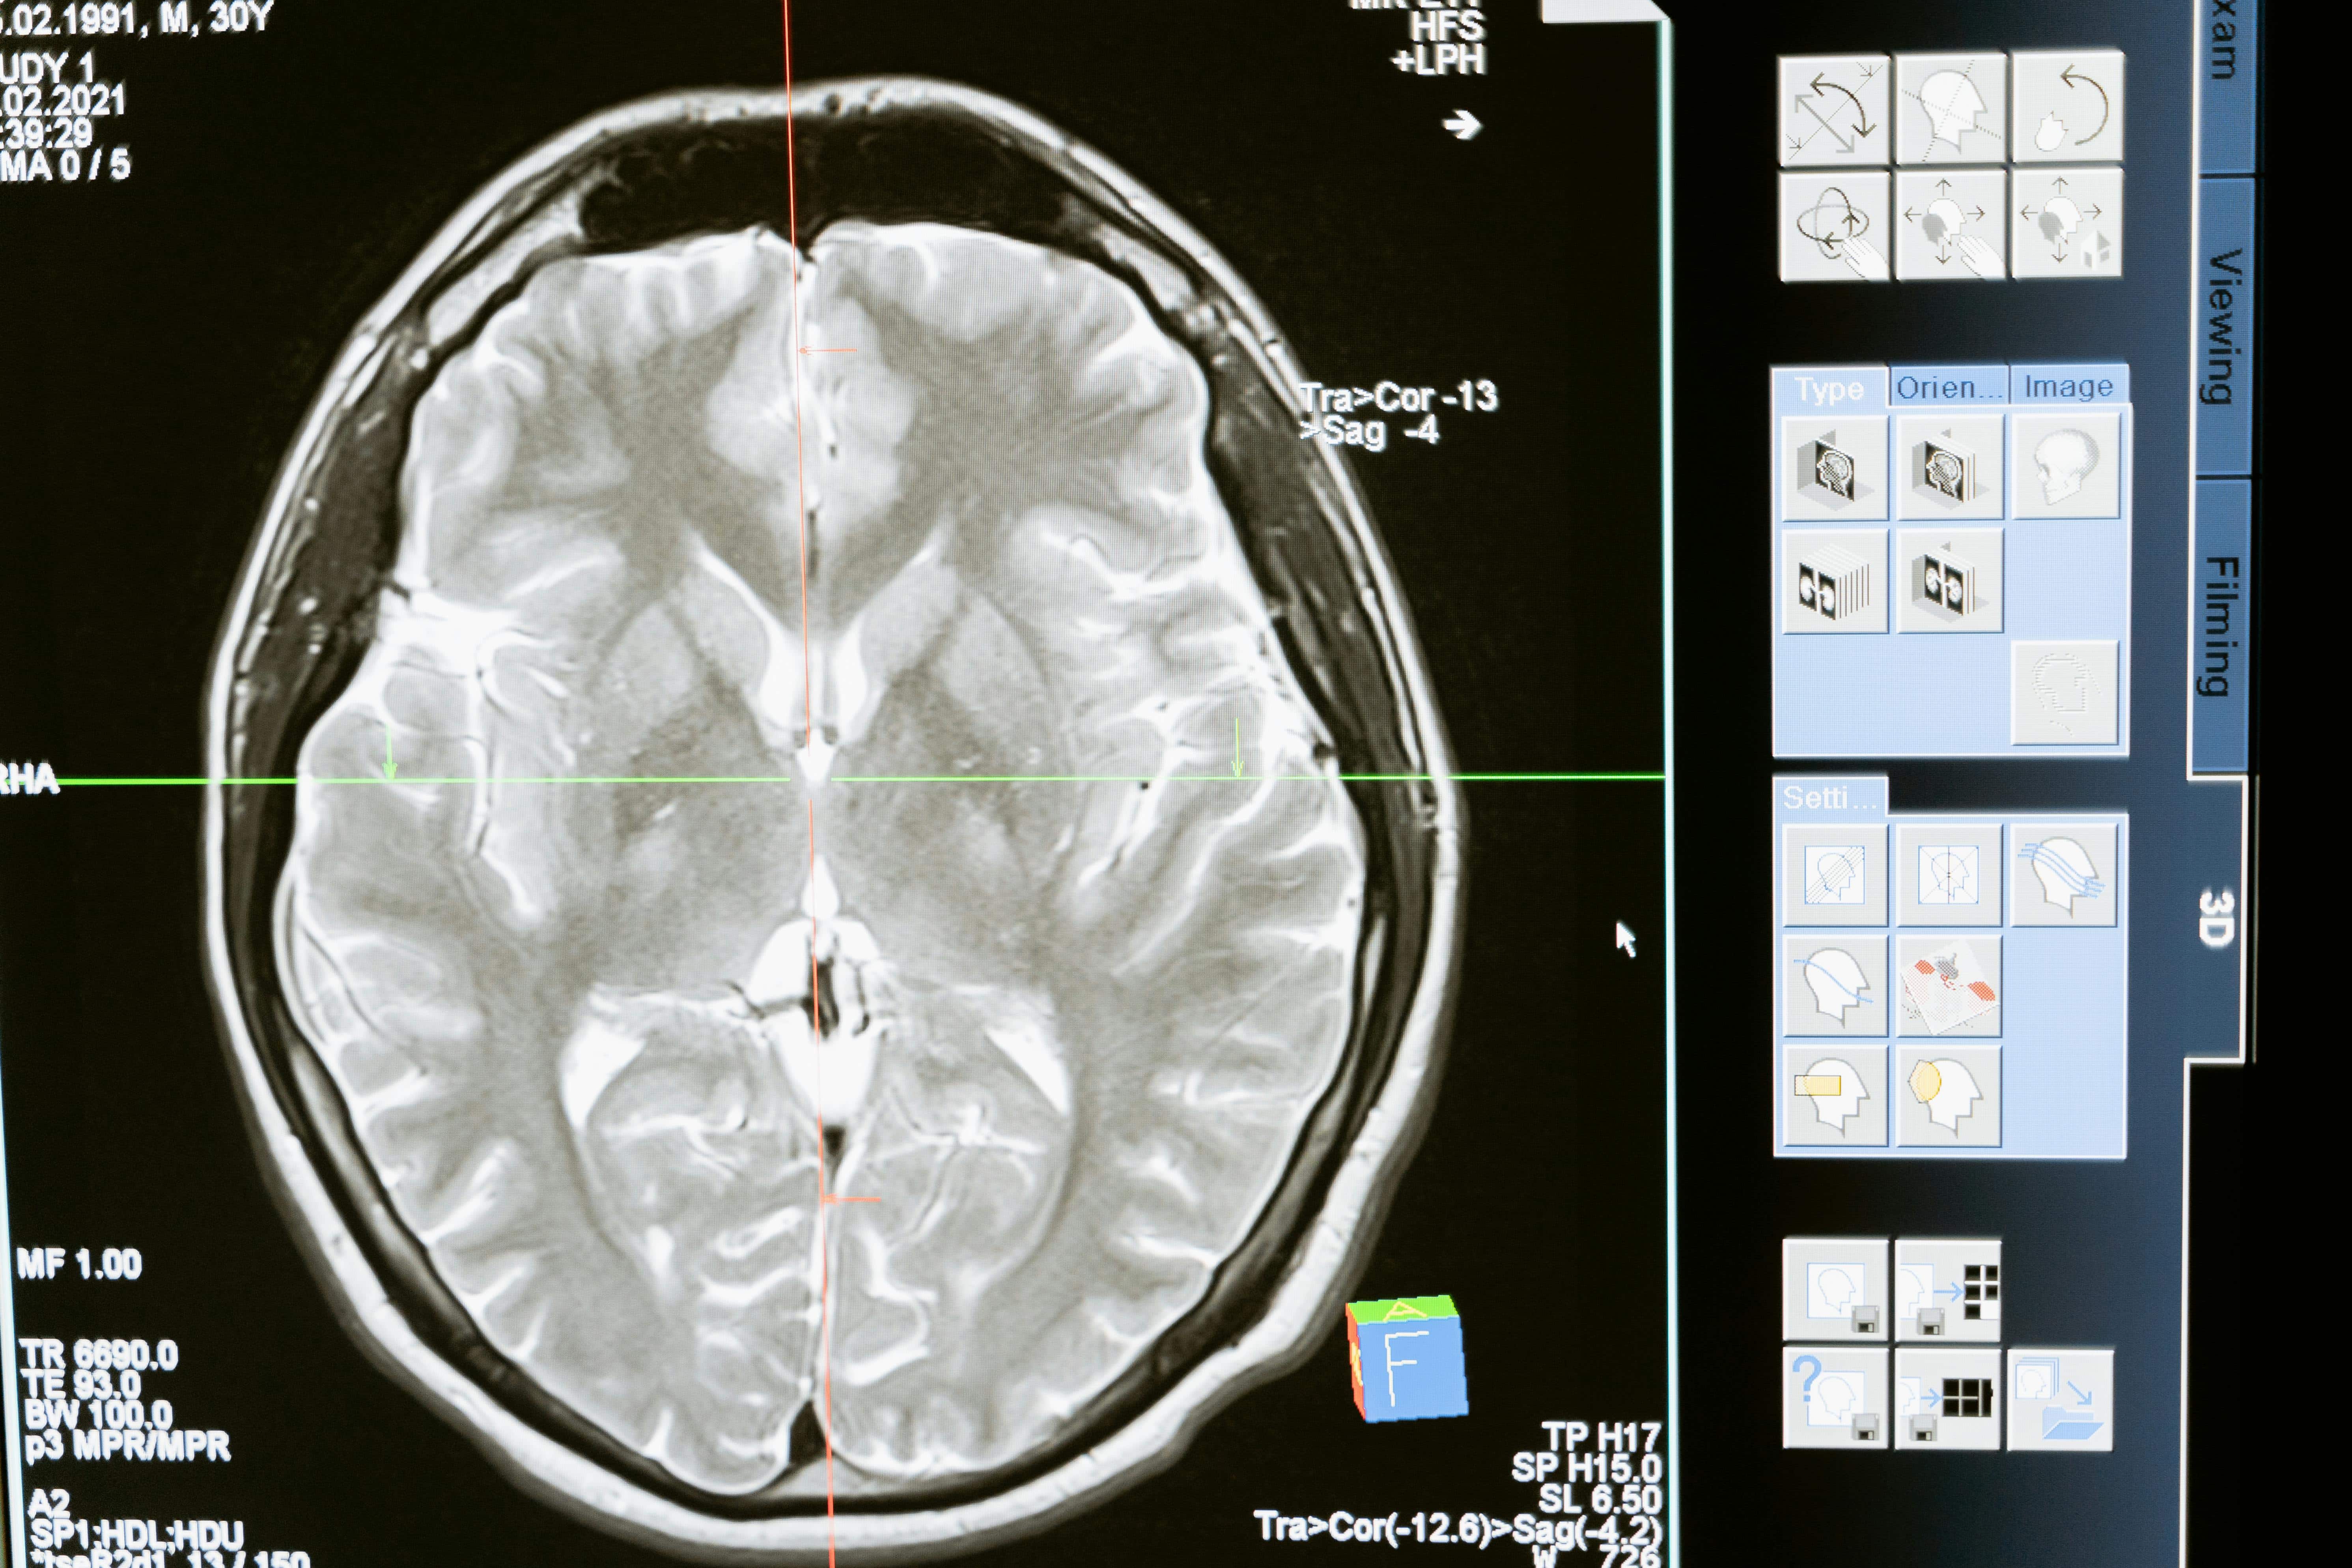

Los investigadores han recurrido a organoides cerebrales humanos (modelos en miniatura del cerebro cultivados en laboratorio) para averiguar cómo esa exposición al plomo en la antigüedad pudo afectar al desarrollo cerebral.